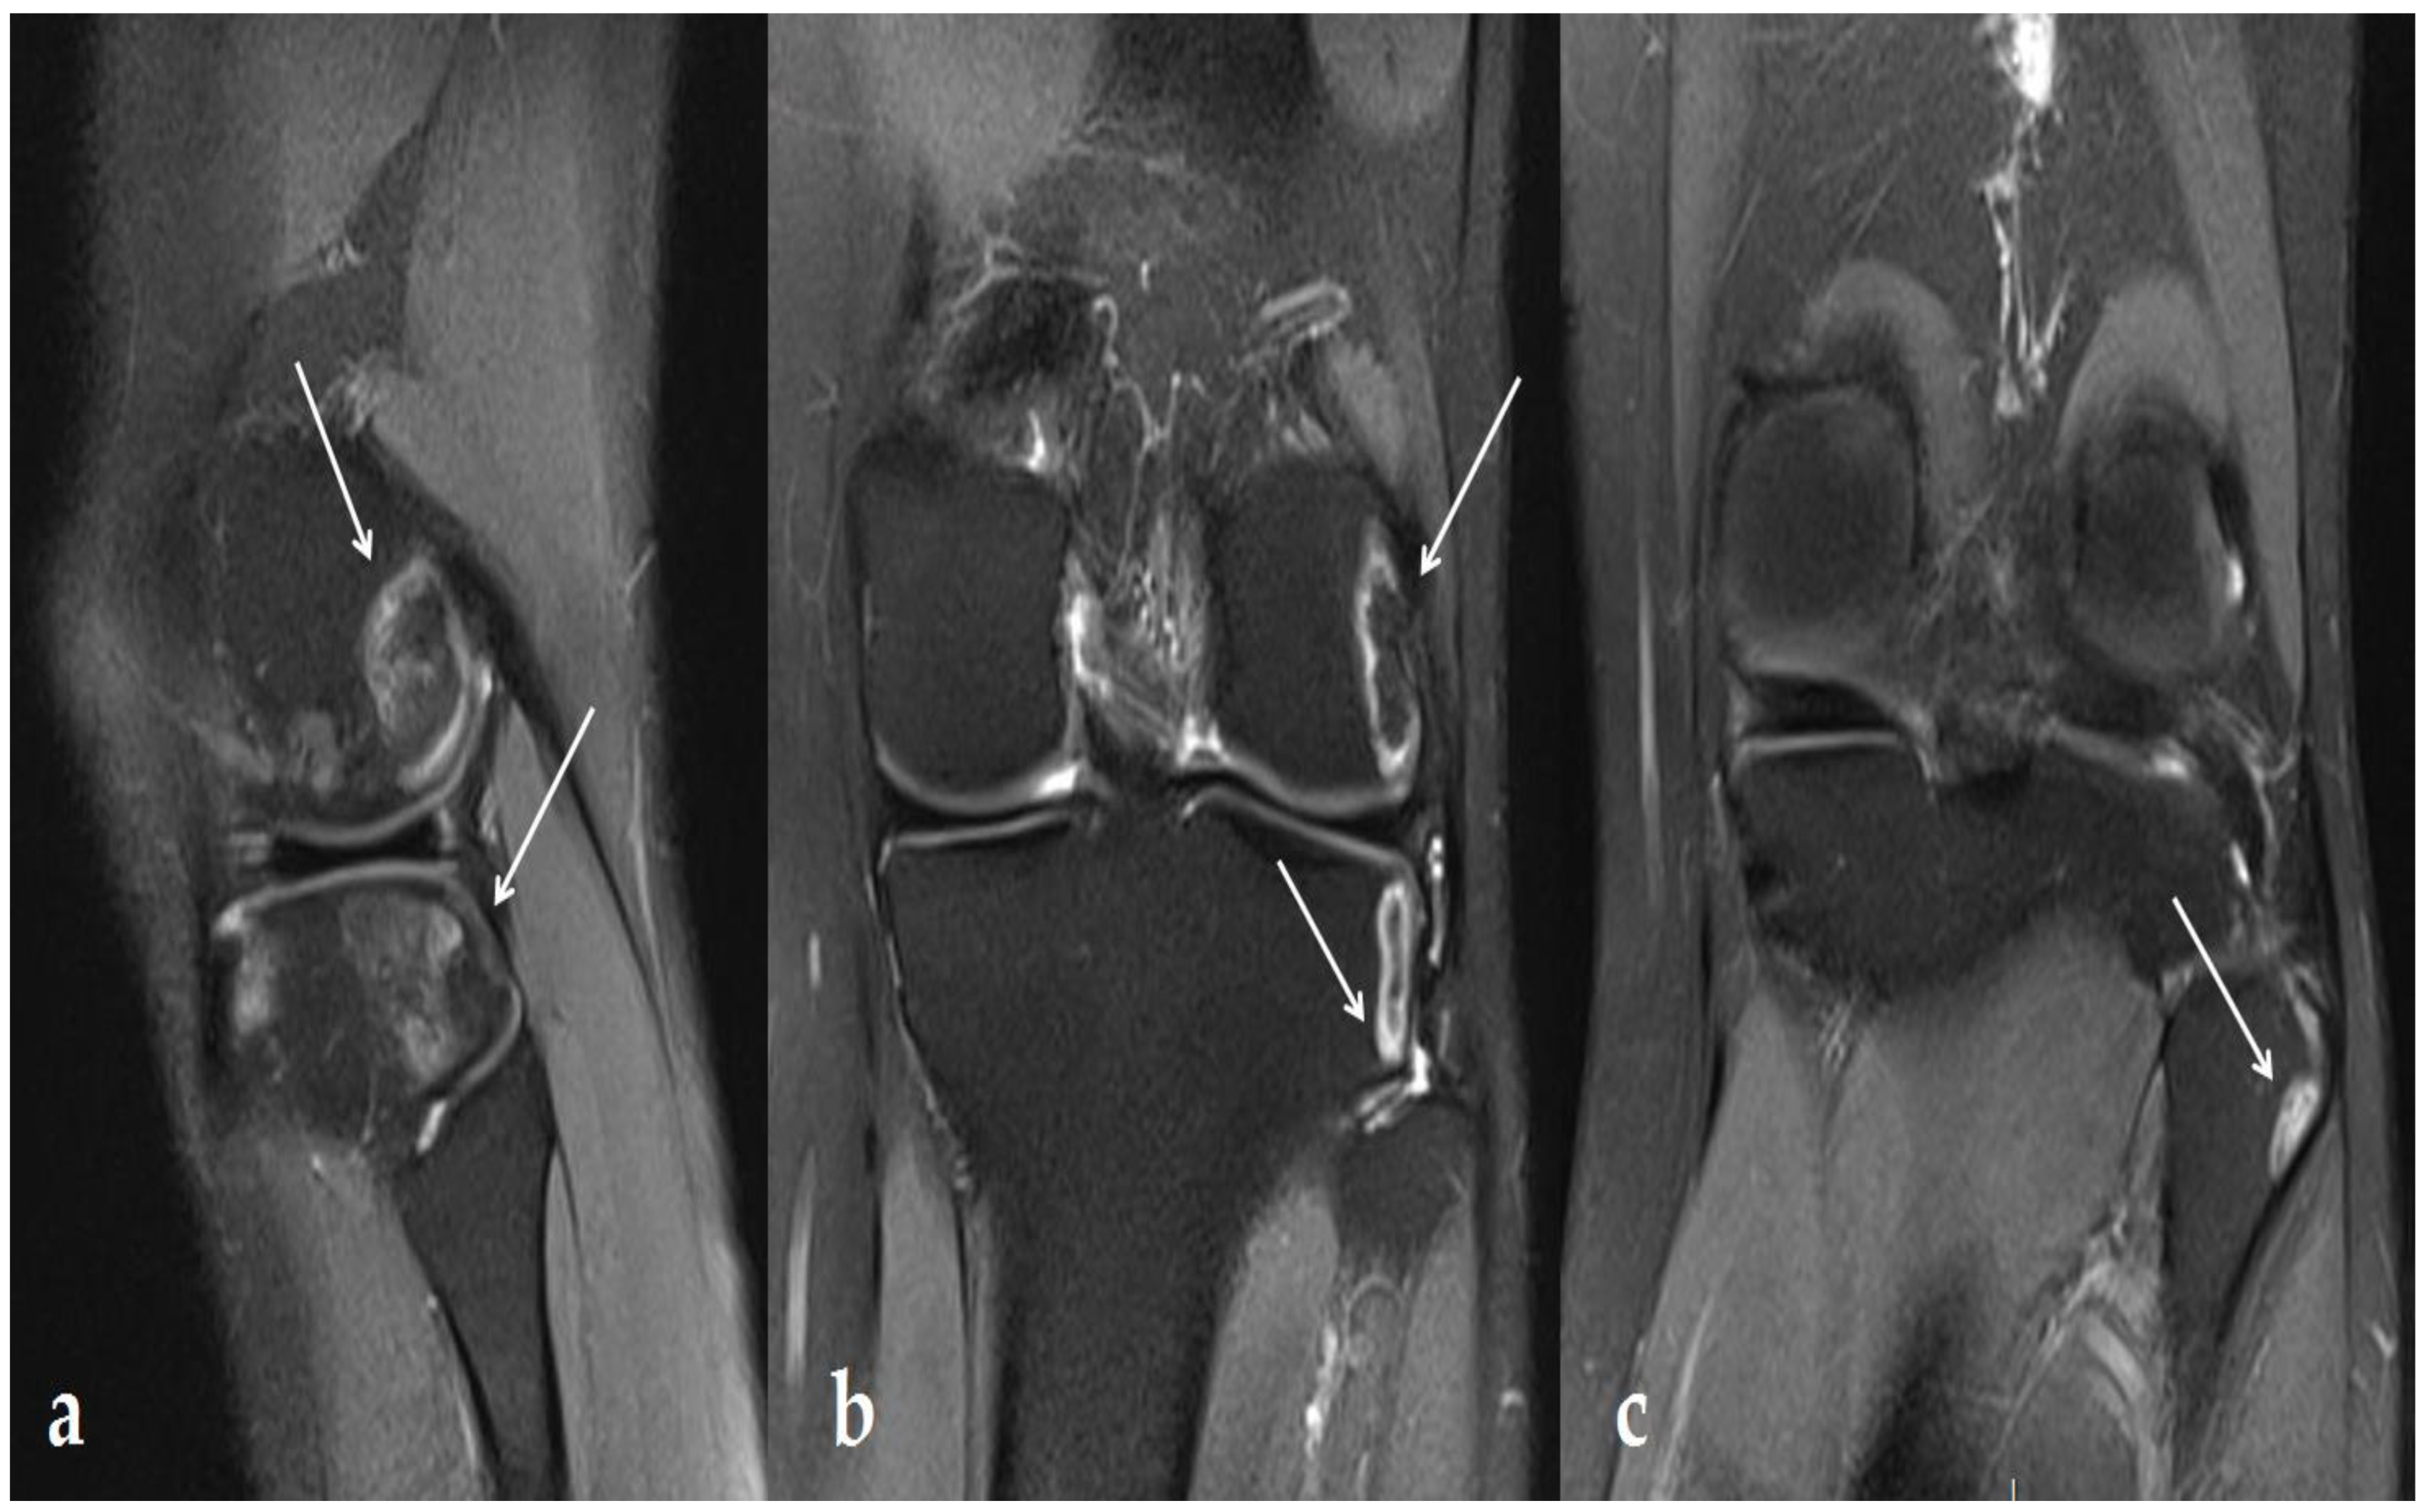

2. Case Report

3.1. Knee Lesions Encountered

3.1.2. Osteonecrosis Lesions of the Knee